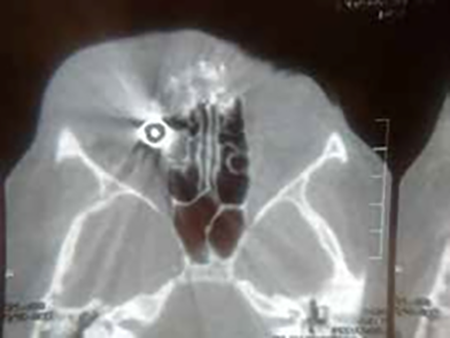

Se solicitaron Rx de cráneo frente perfil, MNP y FNP y tomografía computada, constatándose la presencia de proyectil en ángulo supero-interno de órbita y esquirlas diseminadas. En su pasaje desde su ingreso en la cara anterolateral izquierda y superior de la pirámide nasal el proyectil se fue fragmentando dejando partículas plúmbicas diseminadas. No habiendo signos infecciosos se discontinúa el antibiótico y se mantiene el antiinflamatorio (Figuras 2 y 3).

Figura 2

Figura 3

El 31 de enero de 2019 se reexamina, se evalúan las imágenes de tomografía computada no difiriendo de las obtenidas horas después de incidente. Se palpa dureza en la órbita anterior supero interna El vítreo se va aclarando y comienza a verse retina por sectores la cual está aplicada. Hay una imagen blancuzca del polo posterior y pigmento compatibles con esclera denudada. La proptosis va disminuyendo, interpretando que se debía a sangre en órbita que fue reabsorbiéndose.